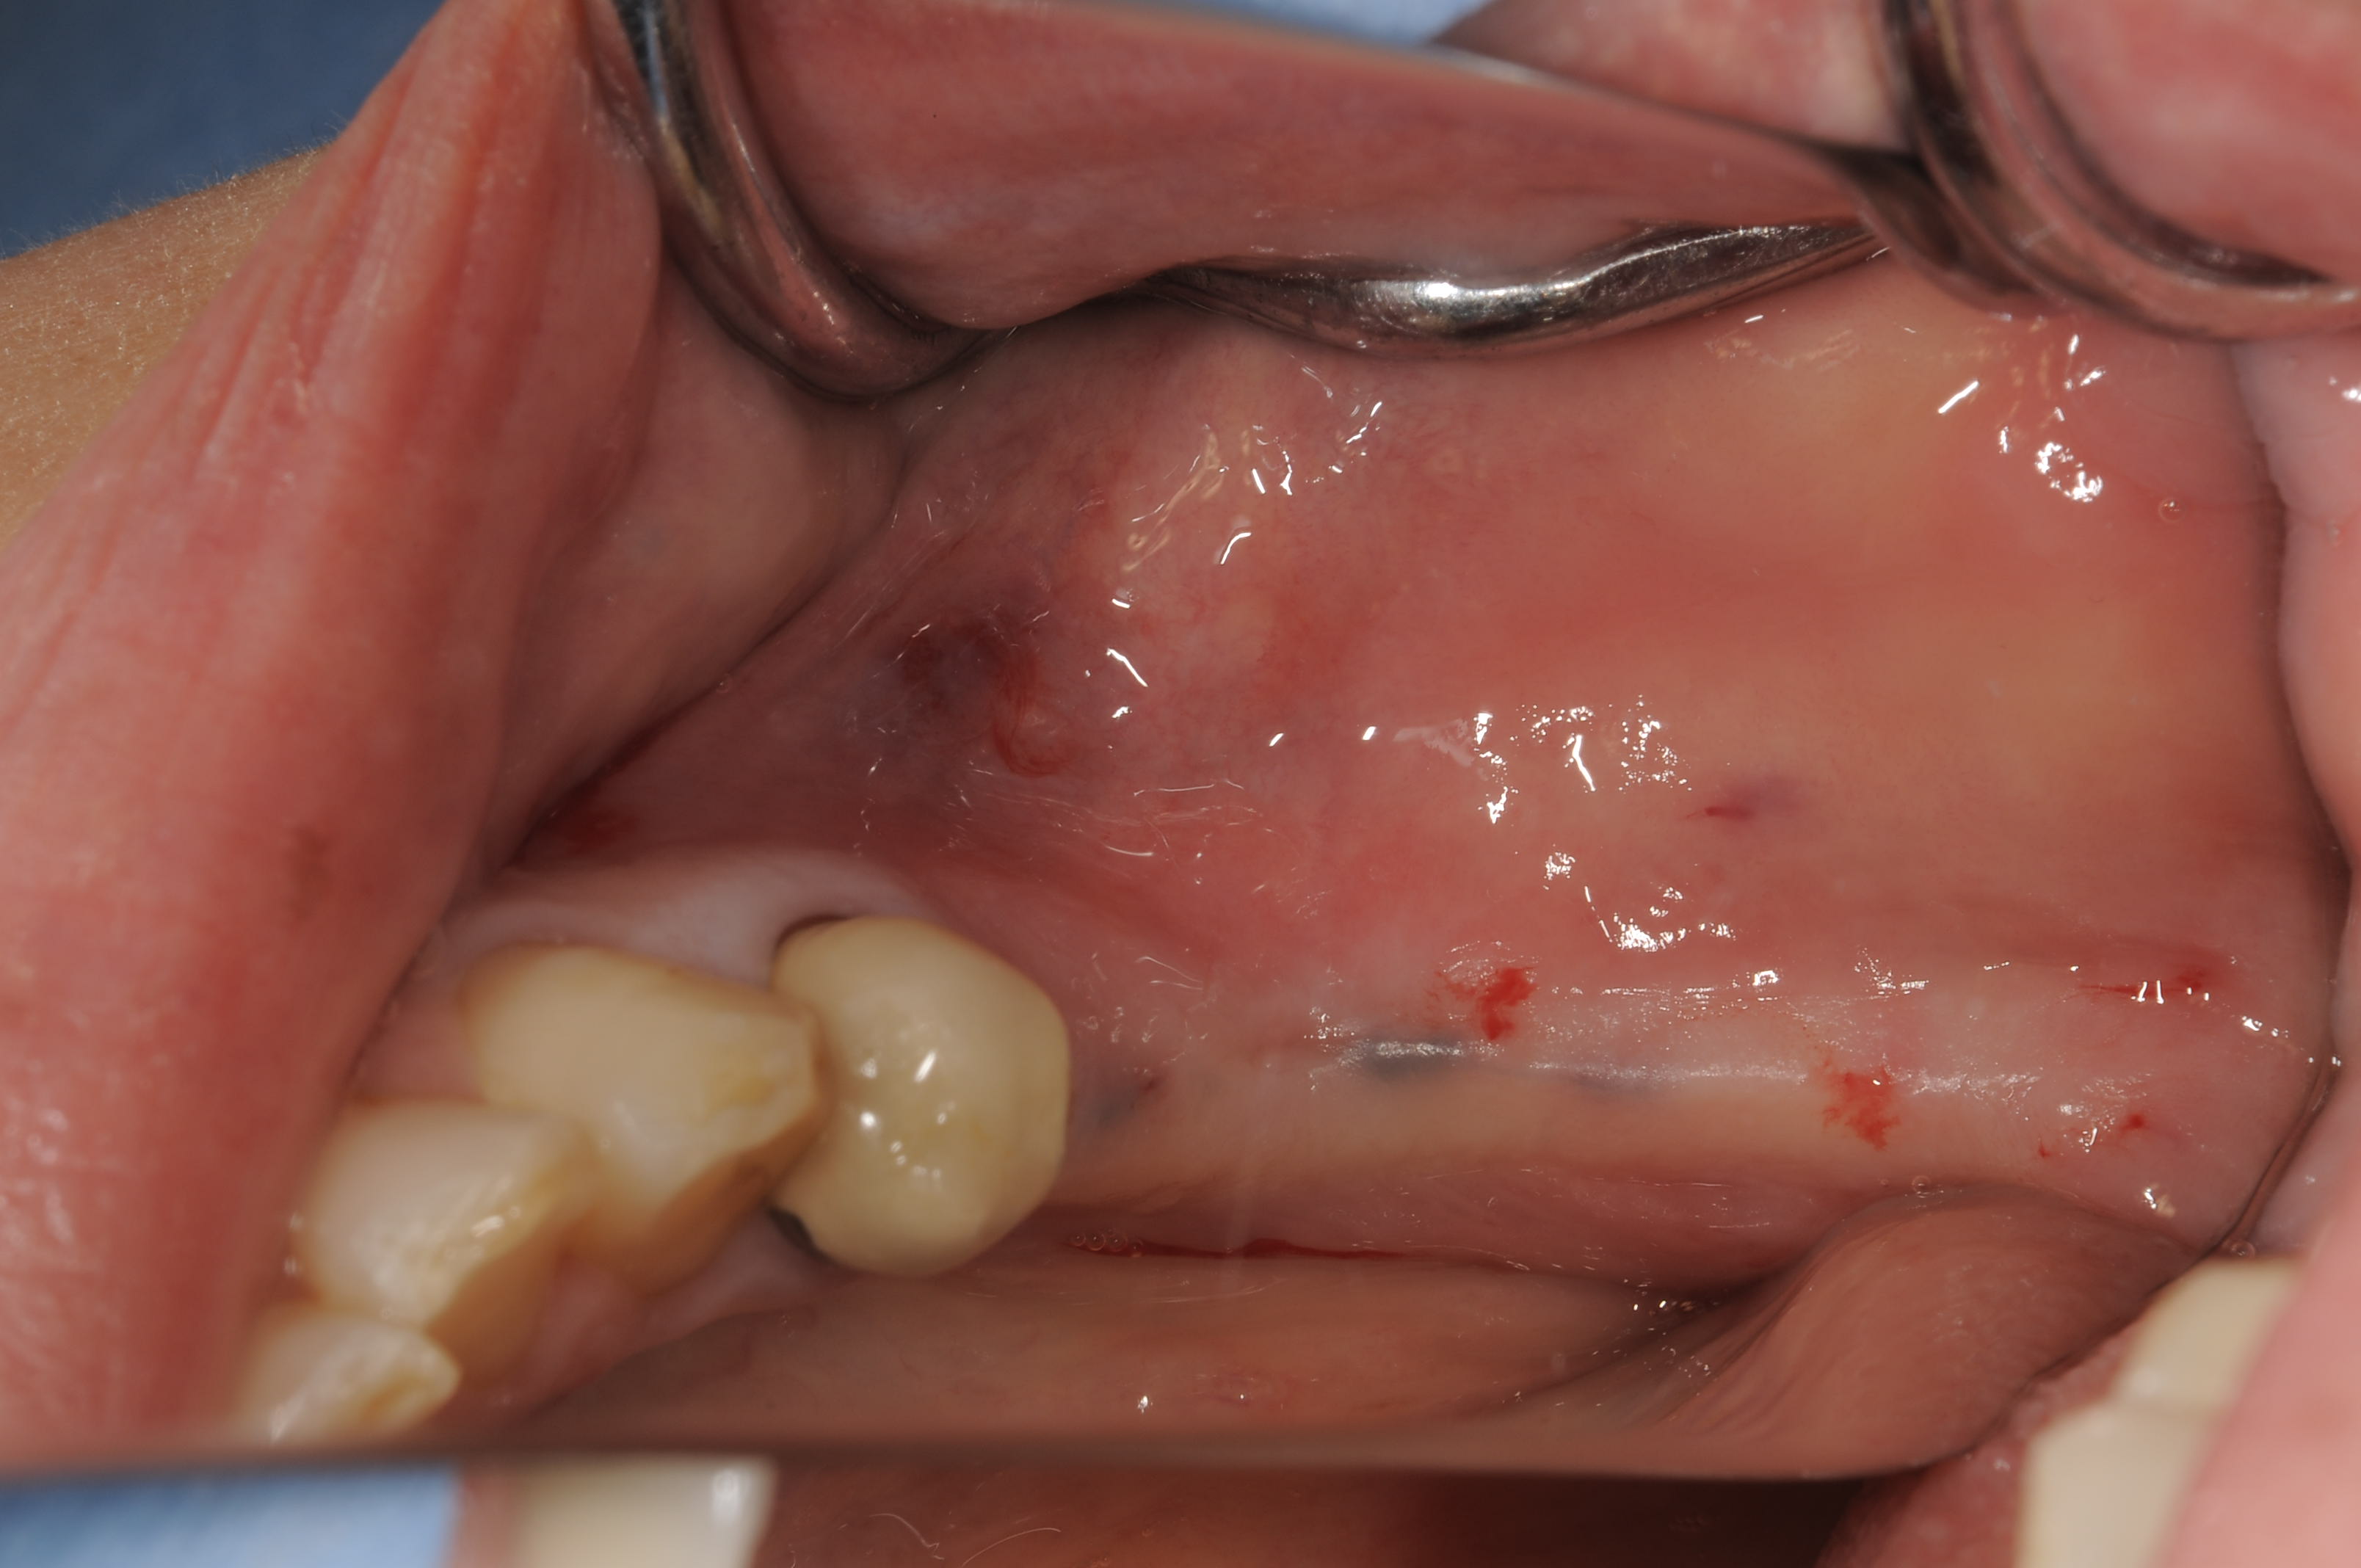

術前の埋入部位です。成熟側です。

歯槽形態は普通で、粘膜も問題ありませんでした。